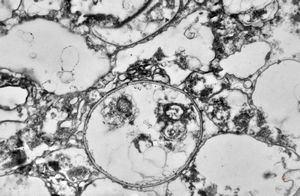

M,50y. | Pneumocystis carinii - lung